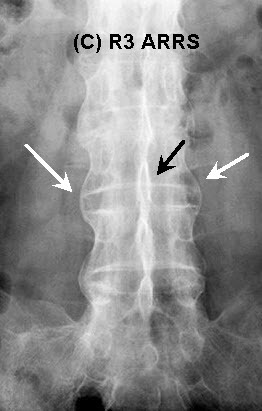

'대나무 척추(Bamboo spine)'라는 용어는 인대증식체(섬유륜의 골화)의 과도한 증식의 존재로 특징지어질 수 있다. 트롤리-트랙(Trolley-track) 징후는 전방 방사선 영상에서 보이며, 극상인대와 극간인대와 골단관절낭의 골화와 일치하는 세 수직 방향의 치밀한 선을 의미한다. 트롤리-트랙(Trolley-track) 징후는 극상인대와 극간인대의 골화를 나타내는 전방 방사선 영상에서 단일 방사선 라인으로 나타나는 단검 징후(dagger sign)에 비해 앞설 수 있다.

△ Trolly Track Sign

(이미지 출처 : http://learningradiology.com/radsigns/radsignspages/T-radsigns.htm)